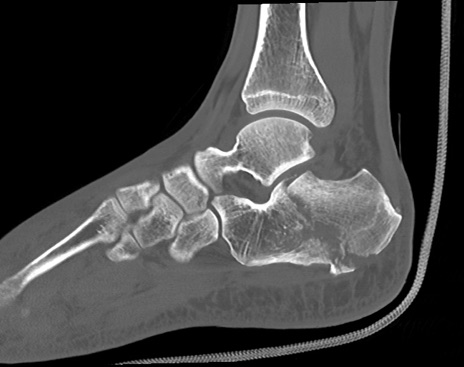

症例37 左足関節CT(矢状断像)

左足関節CT

冠状断像